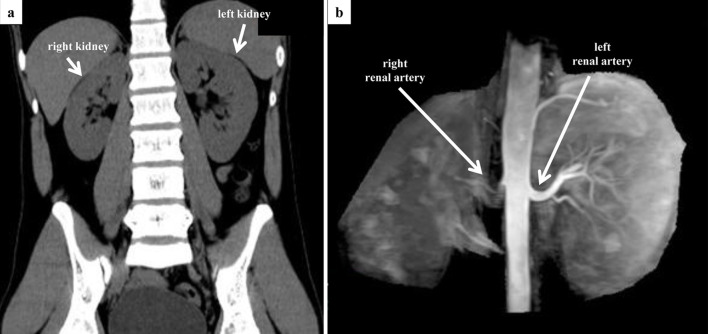

Renovascular hypertension (RVHT) is most commonly caused by renal artery stenosis (RAS) secondary to arteriosclerosis. Other causes of RVHT include fibromuscular dysplasia (FMD) and other rare causes, such as Takayasu arteritis (TA). A male patient in his early 20s presented with hypertension. Laboratory findings were positive for hypokalemia as well as elevations in plasma renin activity and aldosterone concentration. Plain computed tomography revealed atrophy of the right kidney, and magnetic resonance angiography revealed right RAS. A diagnosis of RVHT was suspected, and he was admitted to the cardiovascular ward. After percutaneous transluminal renal angioplasty (PTRA) to treat the right RAS, a typical course was observed with decreased blood pressure, normalizing hypokalemia, and decreased plasma renin activity and aldosterone concentration (which previously were extremely elevated). As angiography showed no remarkable arteriosclerosis of other vessels and given the patient's young age, FMD was suspected as the underlying cause of RVHT. However, the angiographic findings of RAS in the proximal renal artery and the lack of "string-of-beads" appearance were atypical for FMD. The patient had chronic inflammation, and further investigation revealed severe stenosis of the right carotid artery. The high C-reactive protein value and the thickened aortic wall in the computed tomography were the suggestive signs for TA. The patient was diagnosed with TA and started on steroid therapy. Although moderate stenosis remained after revascularization of the renal artery in this patient, hypertension improved markedly, demonstrating the effectiveness of PTRA. Given the diagnosis of TA as the underlying disease, the likelihood of recurrent RVHT due to restenosis of the renal artery remains high, and strict follow-up is thus required.